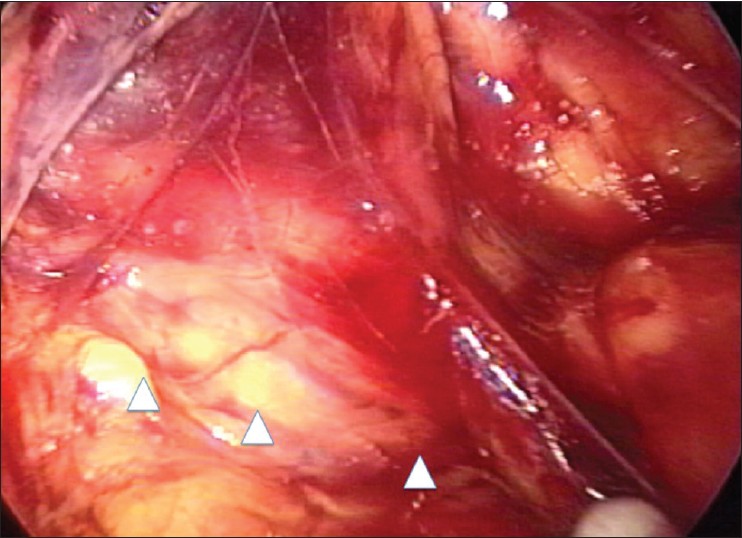

Figure 2: The right testicular vessels (arrow head) were preserved under the anterior renal fascia, but the right ureter was not identified